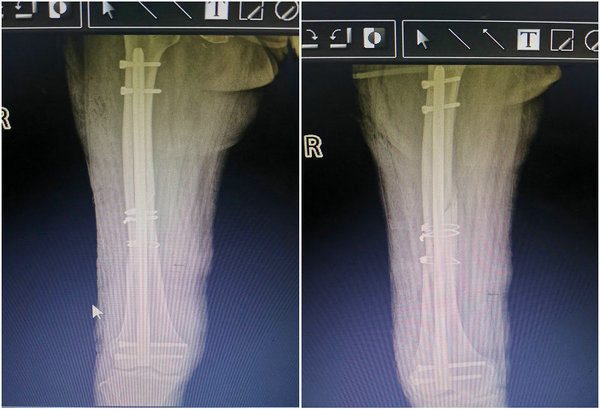

经过了3天的术前准备,乔阿姨的各项指标均调至手术允许的范围内,在与乔阿姨和家属沟通后,朱剑锋主任带领骨外科三病区团队决定为患者行股骨干骨折逆行交锁髓内钉固定术。12月28日8点整,乔阿姨被推进了手术室,麻醉生效后,各项指标仍然正常,手术开始了,首先需要在对患者损伤最小的情况下将碎成4块的管状骨进行复位,复位完毕后再行髓内针固定,经过了3个小时的手术,乔阿姨最后平稳的回到了病房,并进行术后监护。

随着医疗技术的进步,微创手术已成为当今的主流,用髓内针固定长管骨的骨折,可以稳定地保持对位、对线,相应宽度的髓内针可直接紧密地嵌在髓腔周围的皮质骨内层上,使针的横断面能起到良好的弹性固定作用,针的两端又能固定于松质骨中或进针处的皮质骨上,依靠上、中、下三点固定作用而达到骨折的稳定。近年来,在骨外三科朱剑峰主任的带领下,解决了一个又一个的骨科难题,在给予患者最小的创伤的同时又达到了对骨折最稳定的固定。(供稿、摄像:骨外科三病区 刘艳楠 编辑:宣传科 张宁)

骨外科三病区主任朱剑峰(中)为患者行股骨干骨折逆行交锁髓内钉固定术

术后影像